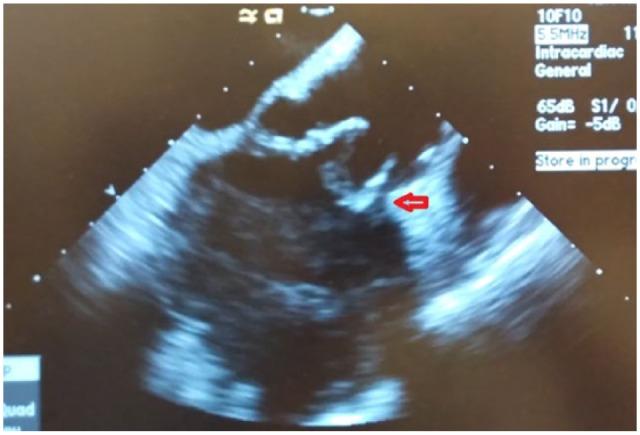

Infective endocarditis (IE) can lead to significant morbidity and mortality without appropriate treatment. Modified Duke Criteria are accepted by many professional societies to establish the diagnosis of IE, and cardiac imaging is one of the major diagnostic criteria. Transesophageal echocardiography is an algorithmic escalation to diagnose IE when transthoracic echo does not appreciate a positive finding. In patients with contraindications to transesophageal echocardiography, cardiac magnetic resonance imaging, cardiac computed tomography (CT), cardiac CT angiography, and fluorodeoxyglucose positron emission tomography with CT or CT angiography may be alternative diagnostic tools. However, these imaging modalities have their own limitations such as local unavailability, the presence of non-magnetic resonance imaging compatible implants, or impaired renal function. Intracardiac echocardiography could be a considerable alternative under those circumstances.

感染性心内膜炎(IE)若未得到恰当治疗,可导致严重的发病和死亡。许多专业学会认可改良的杜克标准用于确立IE的诊断,而心脏成像检查是主要诊断标准之一。经胸超声心动图检查未发现阳性结果时,经食管超声心动图检查是诊断IE的一种逐步升级的检查方法。对于有经食管超声心动图检查禁忌证的患者,心脏磁共振成像、心脏计算机断层扫描(CT)、心脏CT血管造影以及氟脱氧葡萄糖正电子发射断层扫描联合CT或CT血管造影检查可能是可供选择的诊断工具。然而,这些成像检查方法都有其自身的局限性,如当地无法开展、存在与磁共振成像不兼容的植入物或肾功能受损等。在这些情况下,心腔内超声心动图检查可能是一个相当不错的替代选择。